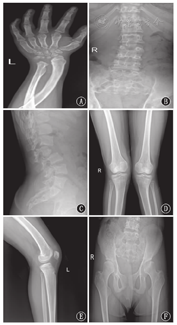

注:指骨(A)、腕骨(A)、肋骨(B)、脊柱(B、C)、膝关节(D、E)、左侧髋臼(F)多发骨发育不良及变形 Multiple dysostosis and deformation were observed in hand (A),wrist (A),ribs (B),spine (B and C),knee-joint (D and E) and left acetabulum (F)

(1)常规化验:血液及尿液常规化验未见异常,肝肾功能、肌酶、碱性磷酸酶正常。(2)骨骼X线检查:四肢骨质疏松,骨小梁结构紊乱,尺桡骨远端关节面及第1掌骨近端关节面骨质粗糙变细,尺桡骨中段向对侧弯曲交叉。桡、尺骨远端倾斜状呈"V"字形。左侧腕部可见8枚腕骨化骨核,腕骨较分散,小而不规则,骨龄相当于正常女童9岁水平(图1A)。胸廓塌陷,双侧锁骨、肋骨略增粗,双侧肋骨远端增宽,脊柱端变细,似船桨(图1B)。脊柱略呈S型弯曲,部分椎体变扁(图1B)。腰椎各椎体骨质密度不均,以L3为中心向左后凸弯,L2椎体后滑,椎体体积变小,前上缘缺如,前下缘呈"鸟嘴样"改变,L1~2椎体向后成角,L1~2、L2~3椎间隙略变窄(图1C)。双膝关节外翻,双侧胫骨近端骨骺线尚未完全闭合(图1D、图1E)。左侧髋臼发育不良,左侧股骨头关节面塌陷,可见不规则骨质破坏,边缘硬化(图1F)。(3)生殖系统超声检查:未见异常。(4)心血管系统检查:心电图未见异常。多次超声心动图显示左心室增大,室间隔及左、右心室壁厚度正常,收缩幅度正常。左心室射血分数为59%~70%。主动脉瓣叶增厚,关闭不良,二尖瓣前叶略厚,瓣尖对合欠佳。心包腔未见异常。提示主动脉瓣大量反流,二尖瓣少量反流,三尖瓣微量反流。